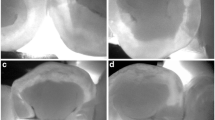

White-light and fluorescence images were captured by a trained examiner using the QP and QC devices in a dark room to maintain image quality. The teeth were brushed with a toothbrush and gauze before QLF imaging to remove dental plaque or debris that could affect the results. The QLF images were captured with a QP (FOV, field of view (W × H × D, mm): 155 × 124 × 103, resolution: 1920 × 1080) using the “occlusal” imaging mode. This device was equipped with a metal tube and plastic shield to block external light and prevent interference with the fluorescence image. Using an intraoral photo mirror, the QP was placed vertically on the maxillary or mandibular occlusal surface containing the tooth to be analyzed and a mirror image was taken (Fig. 4A). The QC (field of view [FOV]: 5–45, resolution: 1280 × 720) was placed perpendicular to the occlusal surface of the corresponding tooth, and images were taken directly (Fig. 4B).

(A) White-light and fluorescent images of the occlusal surface of the maxilla or mandible captured using a Qraycam Pro® (QP, AIOBIO, Seoul, Republic of Korea). (a, b) A trained examiner using a Quantitative light-induced fluorescence (QLF) system in a dark room to maintain the image quality. This device is equipped with a metal tube that blocks external light to prevent contamination of the fluorescent image. (c) White-light image (d) Fluorescent image. (B) (a, b) QLF images of the occlusal surface of the examined tooth captured using a Qraypen C® (QC, AIOBIO, Seoul, Republic of Korea). (c) White-light image (d) Fluorescent image. (C) QA2 version 1.25 (Inspektor Research system BV, Amsterdam, The Netherlands). QA2 provides the QLF parameters (ΔFmax, ΔFaver., ΔRmax, ΔRaver.) of the area of interest (AOI); (a, b) Quantitative analyses of QP and QC images, respectively.